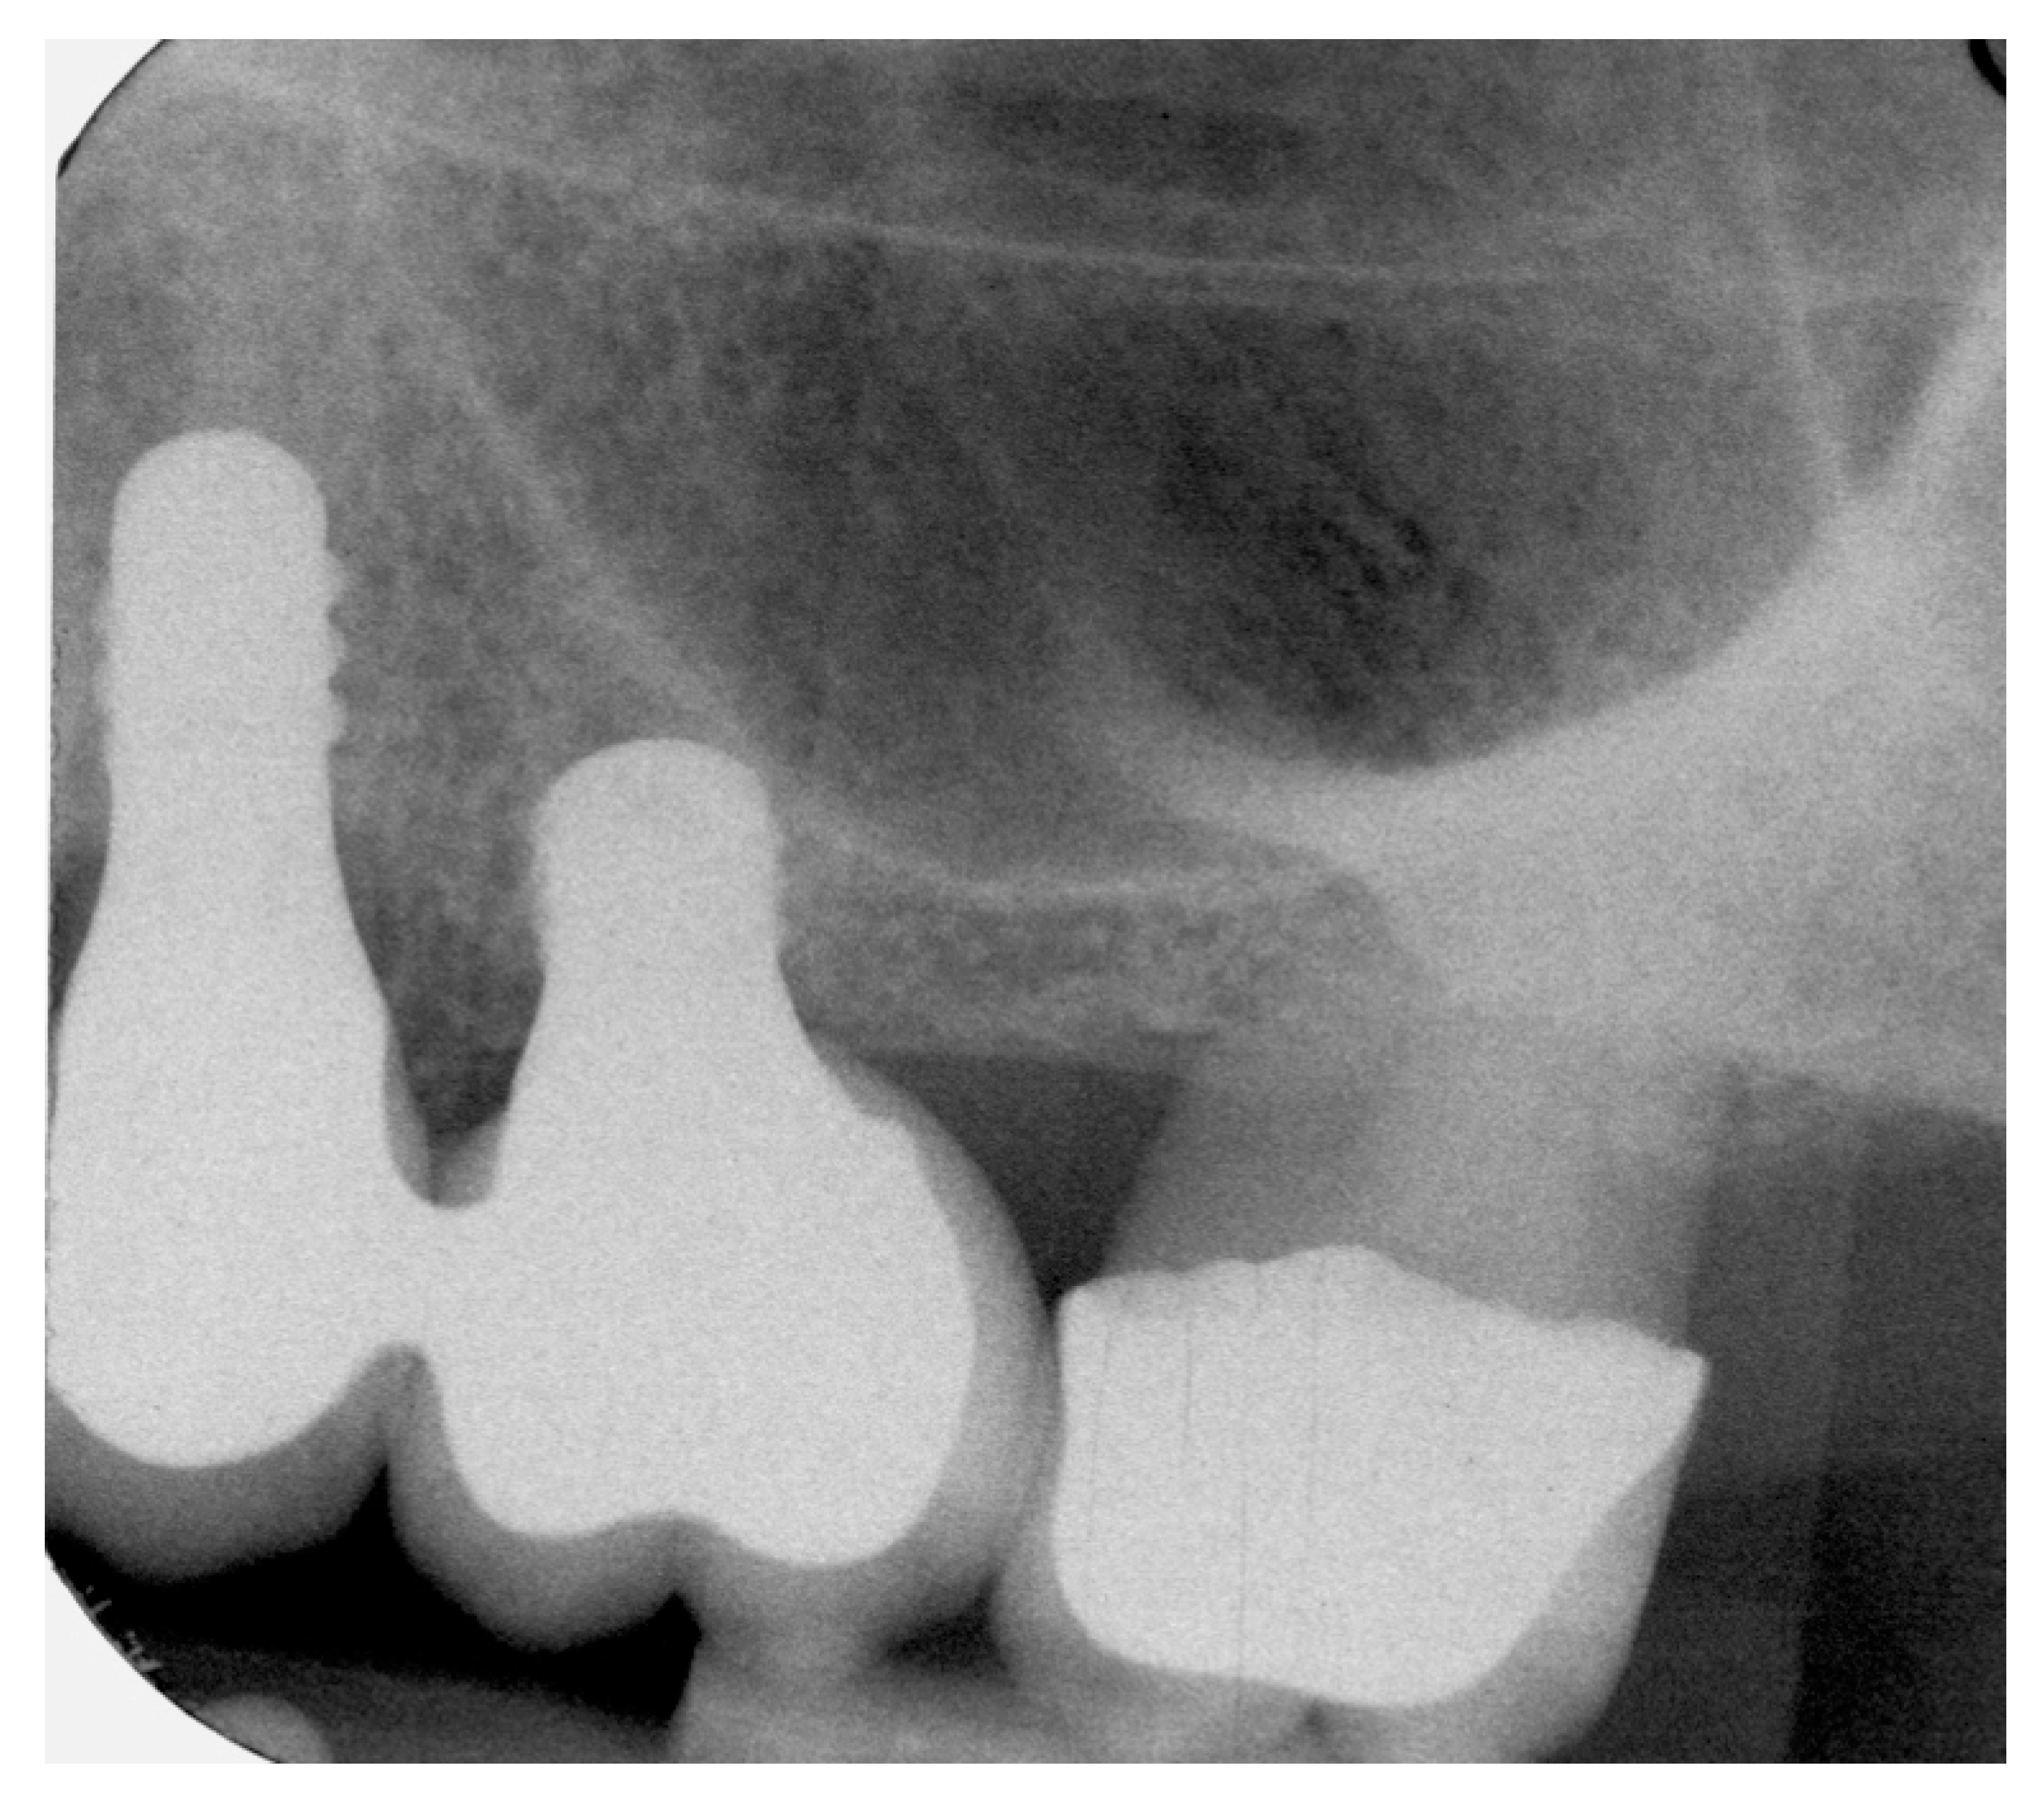

Prospective, Clinical Pilot Study with Eleven 4-Mm Extra-Short Implants Splinted to Longer Implants for Posterior Maxilla Rehabilitation

4.1. Marginal Bone Level (MBL)

4.2. Bone tissue remodeling (MBL change)